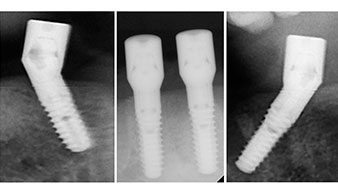

A three-dimensional cone beam computed tomography scan (CBCT, Planmeca) was performed to aid planning and minimize risks. This revealed that the quality and quantity of the available bone were sufficient for the surgery and immediate restoration using the Fast & Fixed method. Following the protocol for this concept, the implants are inserted at 35, 32, 42 and 45. Angling the distal implants by up to 45° shifts the emergence profile to posterior and generates a larger support polygon (Fig. 3).

This corresponds to the next preset position in the Implantmed. Here we see the W&H contra-angle handpiece being held at a 45° angle to mesiocaudal in the region of 45 in order to preserve the mental nerve. The mental foramen is used as the anatomic reference for all drilling in this region. The subsequent holes were drilled at a reduced speed of 300 rpm (Fig. 10 and 11).

Angled abutments (35°) were screwed in to compensate for the divergence of the distal implants, with the result that the emergence profile of all implants was as perpendicular as possible to the bite plane. This is a prerequisite for occlusal placement of the provisional and subsequently the permanent denture (Fig. 15 and 16).